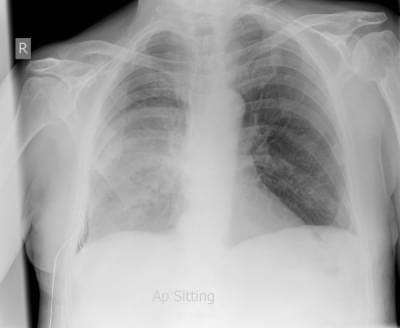

A 36-year-old woman is investigated for lethargy, fever, cough and weight loss. She has been treated by her GP with five courses of antibiotics over the past six months for a combination of chest and sinus infections. Her symptoms, however, have continued unabated. Clinical examination is unremarkable other than some scattered crackles in the right base. She is apyrexial. Urine dipstick: blood ++, protein +.

Her chest x-ray is shown here:

What is the likely diagnosis?